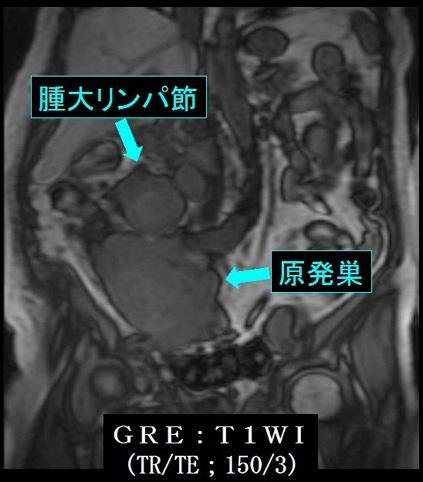

A case of malignant lymphoma which developed at the lower part of the ileum.

Malignant Lymphoma/Malignant lymphoma

Small intestine/Jejunum

MRI

40 -